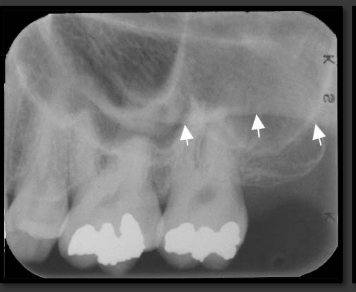

How does the floor of the maxillary sinus present in a radiograph?

It is a thin radio opaque line that travels low near the roots of the teeth.

How does the maxillary sinus present in a radiograph?

It is a radiolucent space that sits above the maxillary teeth.